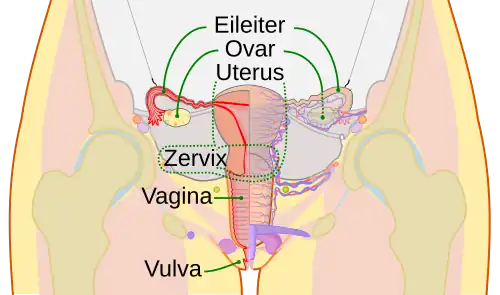

Eileiter

Der Eileiter (lateinisch Tuba uterina, auch Tuba Fallopii; altgriechisch σαλπίγξ Salpinx, veraltet Ovidukt) ist ein paariger Teil der Geschlechtsorgane bei weiblichen Wirbeltieren, welcher als Röhre bzw. Gang beiderseits von der Gebärmutter ausgeht und in der Nähe des jeweiligen Eierstocks endet. Bei Säugetieren ermöglicht er nach der Ovulation den Transport der reifen Oozyte oder Eizelle vom Eierstock in die Gebärmutter. Im Eileiter erfolgt in Gegenwart von Spermien die Befruchtung der Eizelle. Eierstock und Eileiter beim Menschen werden in der Anatomie häufig unter dem Begriff Adnexe zusammengefasst.[1]

Die Eileiter sind beim Menschen etwa 10–15 cm lange Schläuche, die über ein Aufhängeband (Mesosalpinx) an dem breiten Mutterband (Ligamentum latum uteri) befestigt sind. Das nahe am Eierstock befindliche Ende des Eileiters besteht aus einem Trichter (Infundibulum tubae uterinae) mit 20 bis 30, 1 bis 2 cm langen Fransen (Fimbriae tubae, daher auch „Fimbrientrichter“), von denen die mit dem Eierstock verwachsenen als Fimbriae ovaricae bezeichnet werden. Das Infundibulum erweitert sich in die Ampulla tubae uterinae. Diese ist mit 7 cm auch der längste Abschnitt. Darauf folgt eine 2 bis 3 cm lange Engstelle, die als Isthmus tubae uterinae bezeichnet wird. Die Pars uterina tubae uterinae („Gebärmutterteil“) ist der die Gebärmutterwand durchbohrende Teil. Sie ist nur 0,1 bis 1 mm weit und öffnet sich mit dem Ostium uterinum in die Gebärmutterhöhle.[1]